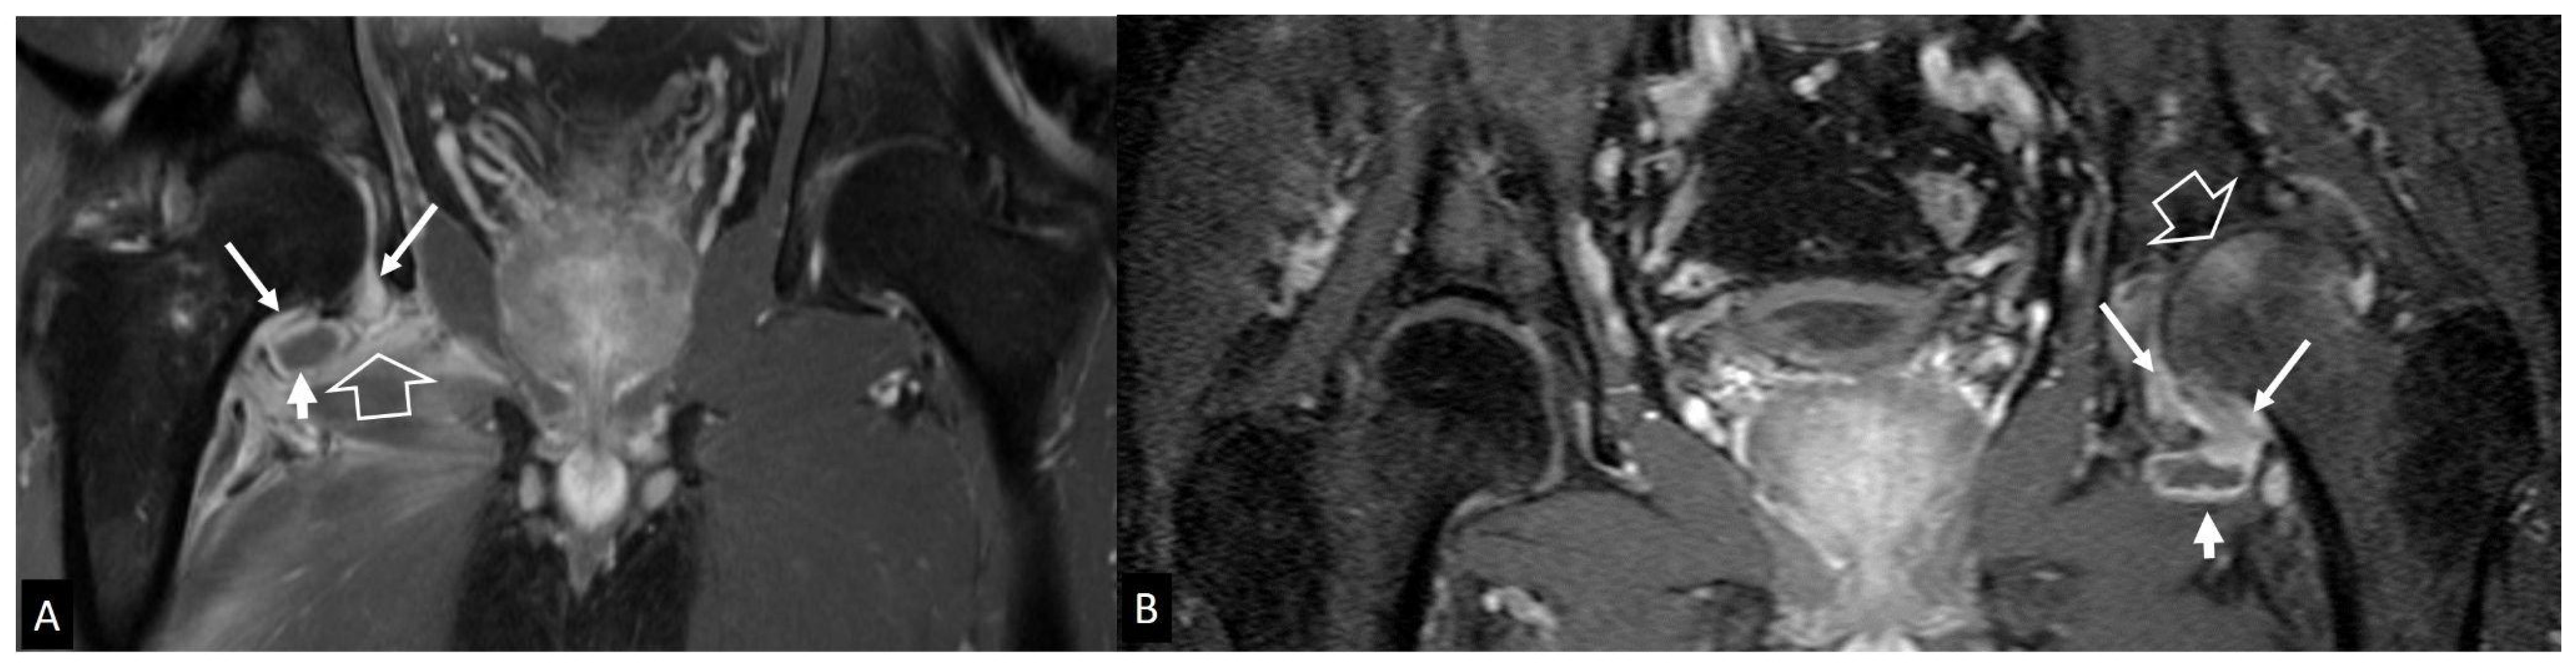

4. Peripheral Joints

4.1. Imaging Features of Septic Arthritis

4.2. Imaging Features of Septic Arthritis Mimickers

4.2.4. Rapidly Destructive Osteoarthritis of the Hip

4.2.5. Neoplasms